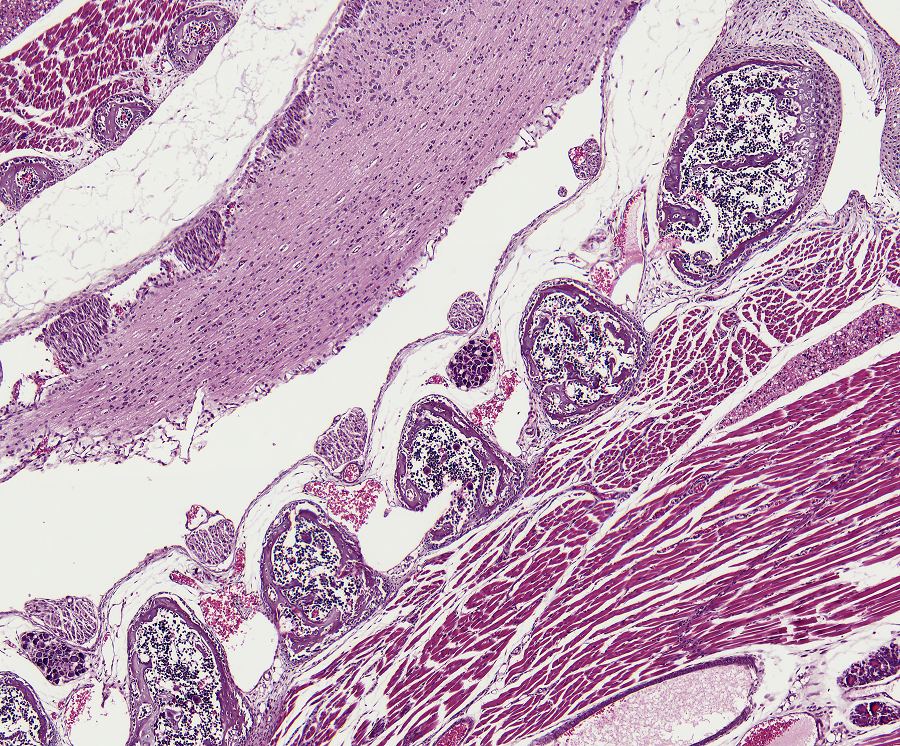

Bone formation or ossification[2] visualized by various histological stains.

Bone can form in two ways:

1. Endesal, in which bone tissue is formed directly from connective tissue; in this case, bone deposition occurs in the form of a band (desmos).

2. Enchondral, in which bone tissue is formed indirectly as cartilage[2] (chondros) is replaced by bone.

In both cases, primary (braided or plexiform) bone is first formed, which is soon replaced by secondary (lamellar) bone, which may have a compact or spongy appearance macroscopically. During bone growth, areas of primary bone, bone breakdown, and secondary bone continually occur side by side. This coexistence of breakdown and creation (remodeling) continues in the adult body, although at a much slower rate.

Bone is composed of cells and intercellular material that is calcified, the bone or bone matrix. Three types of cells can be distinguished:

- Haematoxylin/Eosin[8];